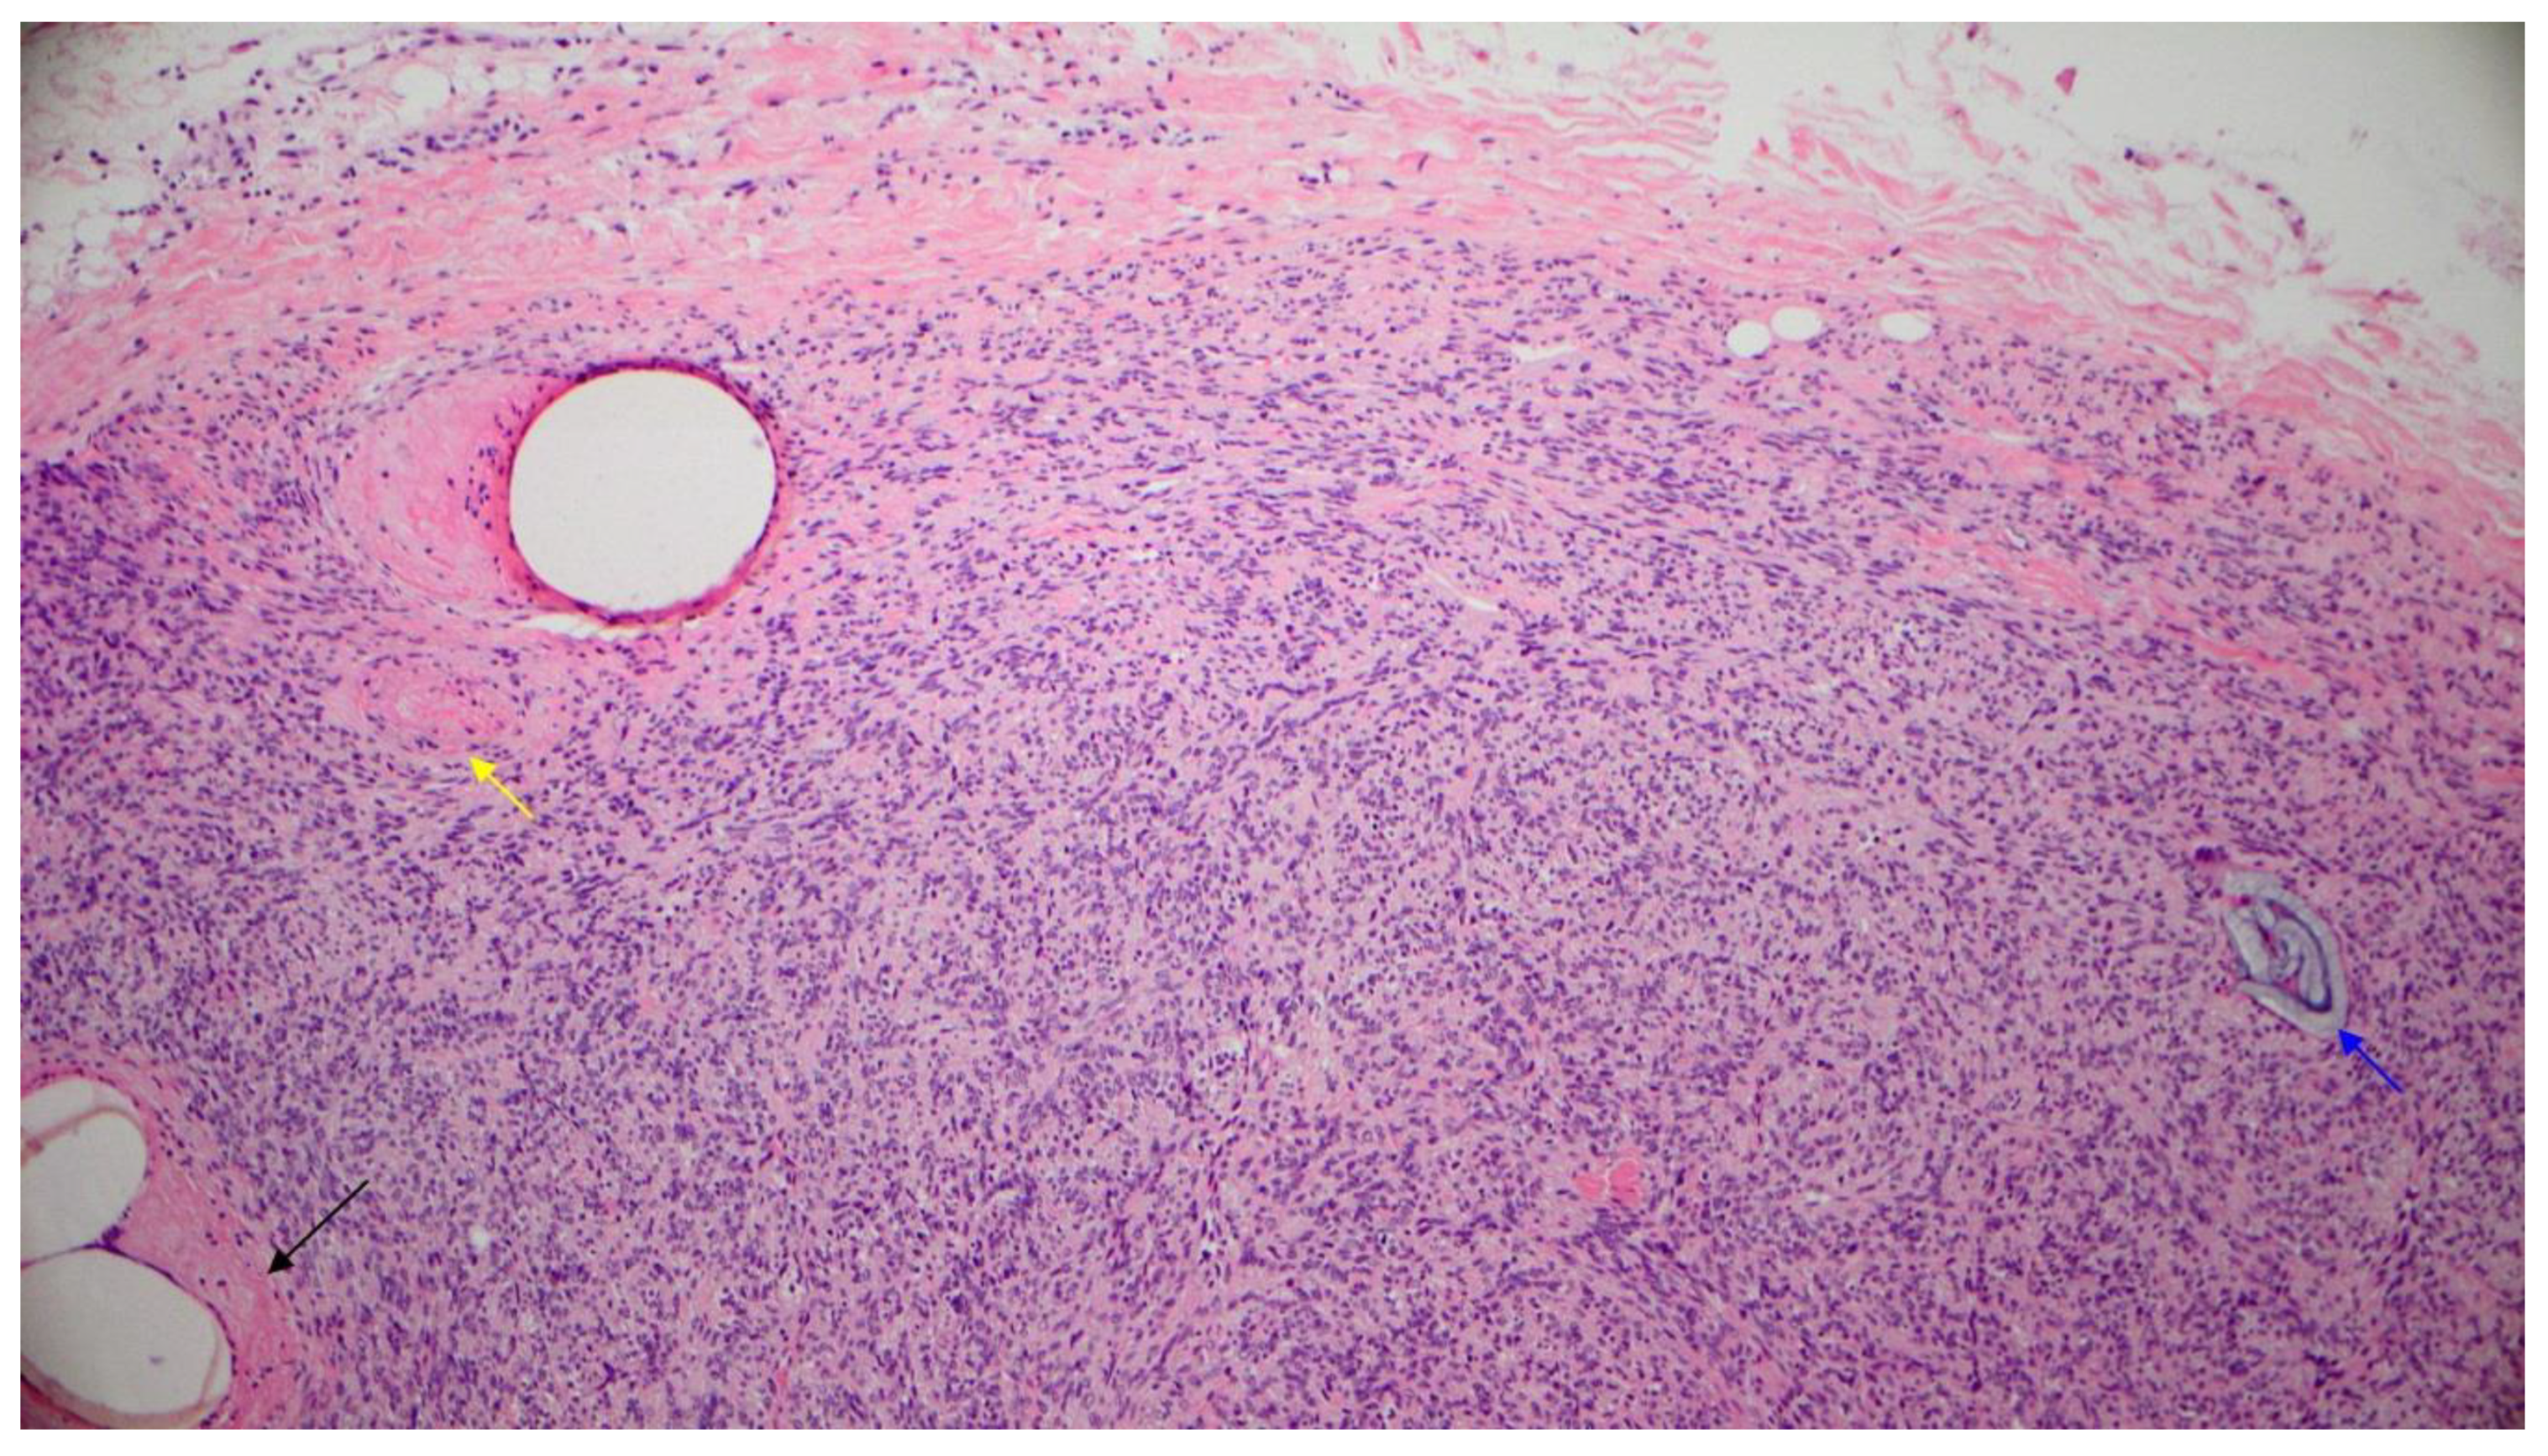

2. Case Report